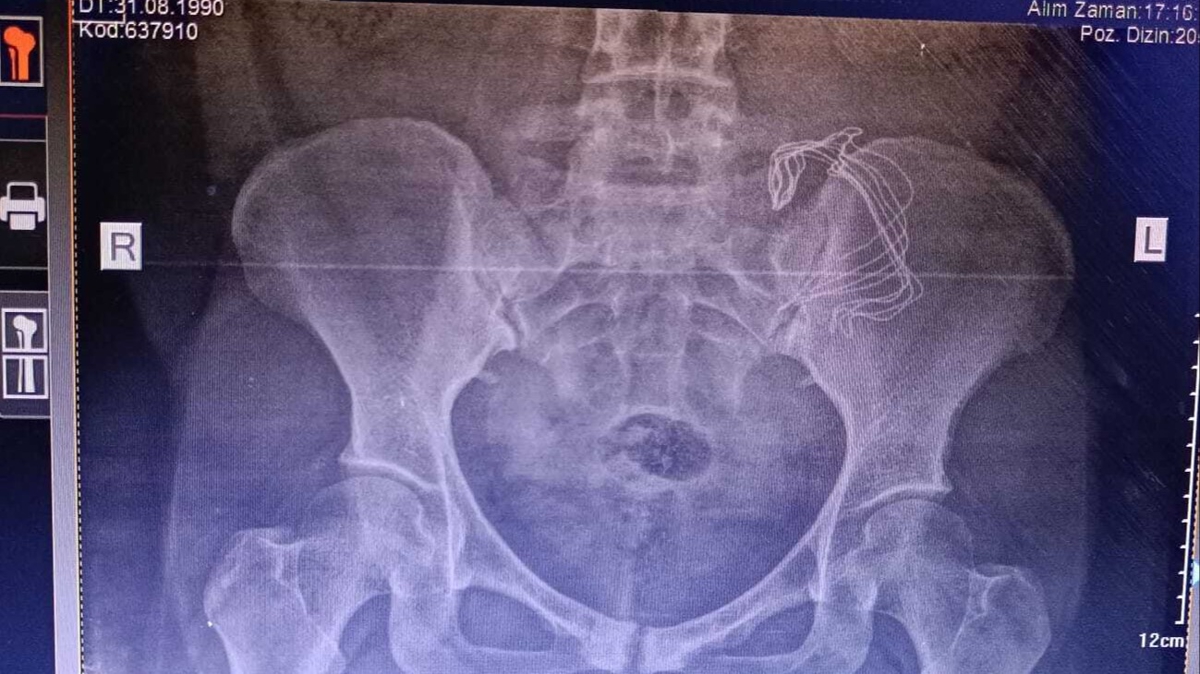

Hastanede yapılan kontrollerde ve çekilen tomografide sonra Frangiz Ergashova ameliyata alındı. Ameliyattan sonra Ergashova'nın karnında doğum sonrası unutulan 15 santimetre büyüklüğünde gazlı bez olduğu ortaya çıktı. Frangiz Ergashova, 10 aydır yaşadığı ağrılara ihmalin neden olduğunu öğrendi. Umut Can ismini verdikleri oğlunun doğumdan sonra 12 gün boyunca küvezde kaldığını söyleyen aile, durumunun şu an iyi olduğunu belirterek hastaneden ve doktordan şikayetçi oldu.

Konuyla ilgili konuşan anne Farangiz Ergashova, "Ağrılarım başladı, akıntı oluyordu sürekli, doğumdan sonra normal olabileceğini düşündüm. 2. doğumumdu. 2-3 ay geçti hala devam ediyor ve iyi değilim, belim ağrıyor. Sonra eşim beni hastaneye götürdü hastanede de aynı şekilde anlattım. Yabancı cismi hissettiğimi söyledim bir ağırlık var dedim, kabız olabilirsin dediler. Bana antibiyotik yazdılar. İlaçlar antibiyotik olduğu için emziremedim çocuğu ve sürekli mamayla besledik. Ağrılarım olduğu için çocuklarımı bakamıyordum. Başka bir hastaneye gittik sertliği söyledim, tomografi çekildi, ameliyat olmanız gerekiyor dediler. Ameliyatta sargı bezi gibi bir şey çıktı ve iltihaplanmış. 15 cm sargı bezi var dediler. Sargı beziyle gezmişim, İçimde iltihaplanmış. İki çocuğum annesiz kalabilirdi. Ölümden döndüm diyebilirim" dedi. Hastane yönetimi ise iddialara cevap vermedi.